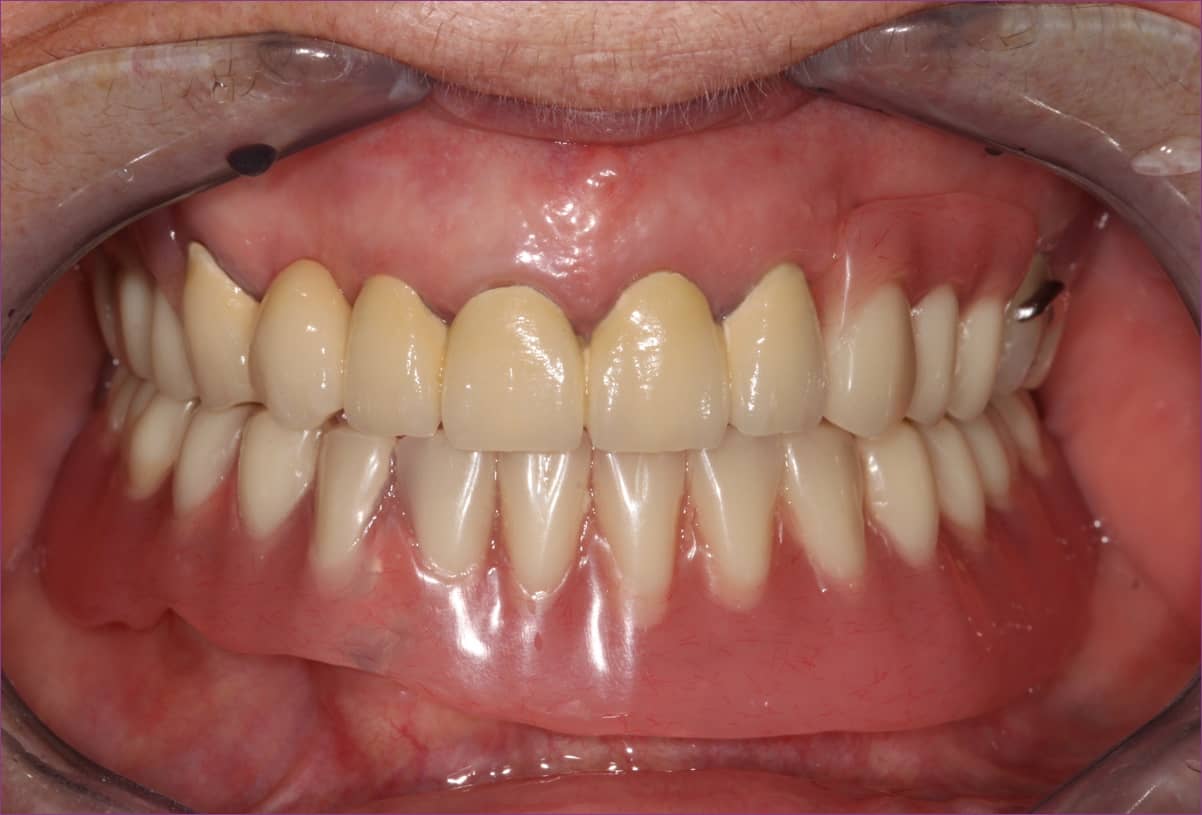

Végül a kezeléssorozat végén átadásra kerültek a fogpótlások. Az összkép a megérkezési állapottal összehasonlítva drámai változásokat mutat.

Ám a legnagyobb meglepetés mégsem ez volt a páciens számára!

A kezelés után ugyanis az idős hölgy krónikus fájdalmai enyhülni kezdtek, majd az évek óta fennálló fej- és nyakfájása teljesen megszűnt, az ízületi panaszokkal egyetemben.

Nem csoda, hogy ilyen elégedett a mosolya, hiszen a megújult fogsora mellé „grátiszként” még a krónikus fájdalmai is elmúltak…